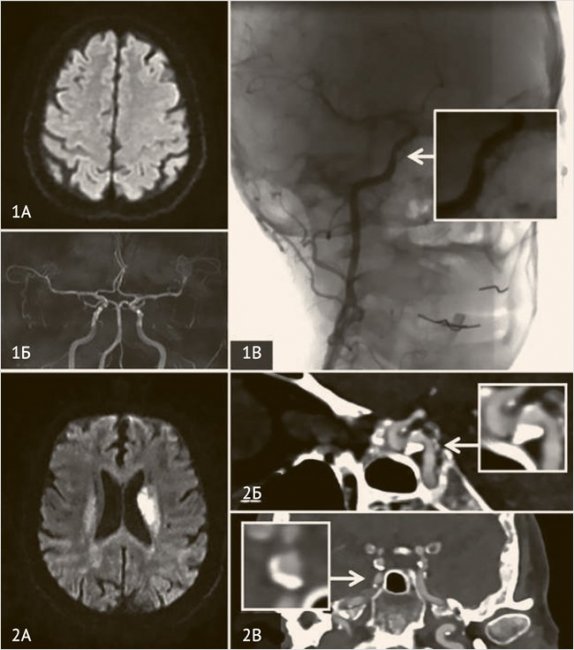

Рисунок 2. Нестенозирующий атеросклероз сонных артерий

Мужчина, 70 лет, перенес ESUS с эмболией сегмента М2 правой средней мозговой артерии (А) в период подготовки к плановому коронарному шунтированию. В результате тромбоэкстракции восстановлен кровоток TICI III (Б), получен эмболический материал (В). Неврологический дефицит полностью регрессировал. Патогистологическое исследование эмбола позволило верифицировать фрагмент бляшки с тромбом (Г). Таким образом, ипсилатеральный стеноз внутренней сонной артерии 40% (Д) был признан симптомным, так как бляшек в восходящей аорте и интракраниальном русле выявлено не было.

На 6-е сутки после тромбоэкстракции пациенту проведена симультанная операция – каротидная эндартерэктомия и коронарное шунтирование на работающем сердце. Наблюдение в течение двух лет не выявило повторных ишемических событий.

Рисунок 4. Интракраниальный атеросклероз

Пациентка, 58 лет, поступила в клинику с левосторонним гемипарезом. Проведен внутривенный тромболизис с положительным клиническим эффектом, очаг инфаркта на DWI МРТ (1А) не сформировался. 3D-TOf МРангиография (1Б) в норме, другие большие источники эмболии исключены. По результатам селективной дигитальной ангиографии выявлен стеноз сегмента С6 правой внутренней сонной артерии 30% по методу WASID (1В), расцененный как симптомный. Пациент, 62 года, перенес ишемический инсульт в бассейне левой средней мозговой артерии (2А). По данным КТ-ангиографии выявлена бляшка сегмента С5 внутренней сонной артерии слева (2Б, 2В), которая из-за феномена позитивного ремоделирования стенозирует просвет артерии на 40% (WASID); других больших источников эмболии выявлено не было.